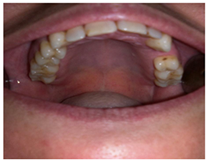

- Se realizará una revisión previa con apoyo de una ortopantomografía para ver el estado general de las piezas dentarias y el estado periodontal.